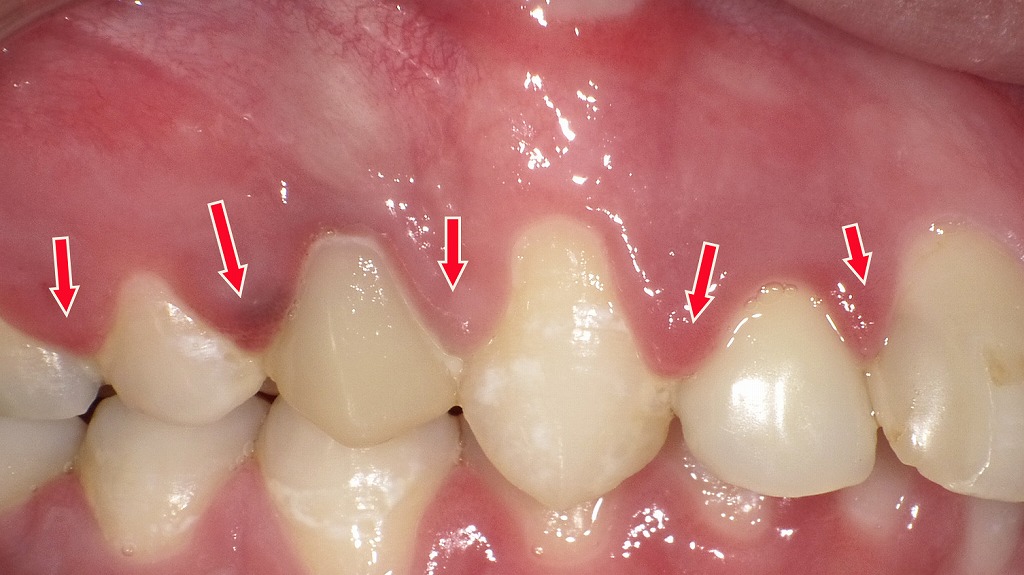

この画像は、同症例の上顎前歯部における歯周外科手術(フラップ手術)の術中写真です。

歯肉を剥離し、歯根面および骨の状態を明視下で確認している場面です。

🔍 手術の概要

- 術式名:歯周外科手術(フラップ手術)

- 目的:歯周ポケット内の歯石除去・感染組織の除去・歯槽骨形態の整形・再付着の促進

🦷 観察される所見

- 歯肉弁の剥離

- 歯肉を切開し、骨膜下で剥離して歯根面と歯槽骨を露出しています。

- 歯肉縁が大きく開かれており、歯槽骨の吸収範囲を直接確認できる状態です。

- 歯槽骨の吸収

- 特に中切歯および側切歯部で歯槽骨の吸収が明らかです。

- 骨頂が歯根の中間1/3付近まで低下しており、中等度〜高度の骨吸収が示唆されます。

- 歯根面の露出

- 歯根表面には歯石沈着やセメント質の変色が見られ、徹底的なデブライドメント(スケーリング・ルートプレーニング)が必要な状態です。

🩺 臨床的意義

- この手術は、中〜重度歯周炎で深い歯周ポケットや不良肉芽組織が存在する場合に実施されます。

- 視野を確保することで、歯根面の完全な清掃と骨整形(オステオプラスティー)が可能となり、歯周組織の再付着や歯肉の健康回復を目的としています。